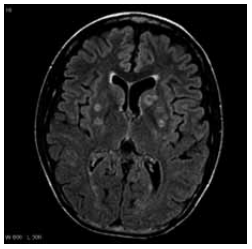

Paciente do sexo masculino, de 49 anos, portador de HIV diagnosticado há dez anos, interrompeu a TARV há três anos. Procura o pronto-socorro com cefaleia progressiva há quatro semanas, associada a febre, sendo internado na unidade de terapia intensiva por confusão mental e fraqueza em hemicorpo esquerdo. Ao exame físico: desorientado, paresia grau 3/5 em membro superior esquerdo, sem rigidez de nuca. Realizou a ressonância de crânio mostrada a seguir:

Enunciado 4918796-1 (Arquivo pessoal; imagem usada com autorização)